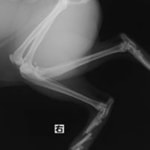

症例3:キルシュナーワイヤーのピンニングによる整復

ペルシャ猫 11ヶ月齢 雄

他院にて左大腿骨遠位の成長板骨折(salter-harrisⅠ型)が認められており、治療相談を目的として来院。当院にて、キルシュナーワイヤーを用いたピンニングにより骨折部位の整復を行いました。術後の経過は良好で、現在も経過観察中です。

術前レントゲン

術後レントゲン